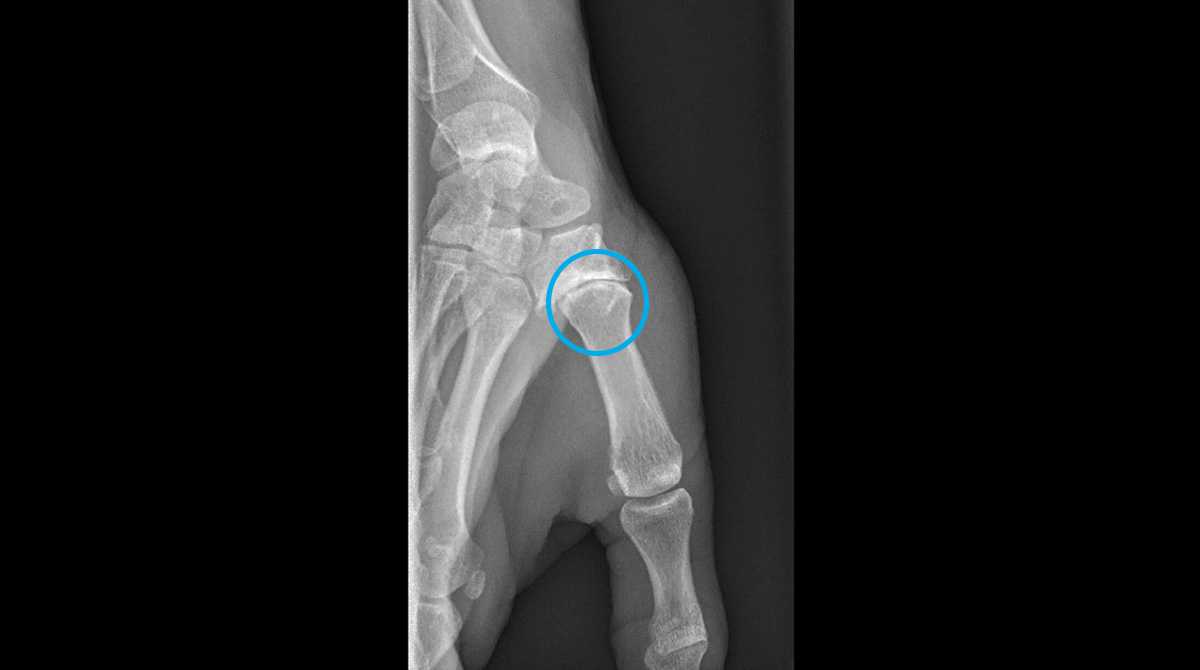

La radiographie standard est l’examen de choix pour établir le diagnostic, à la recherche de signes d’usure du cartilage de l’articulation trapézo-métacarpienne.

La présentation clinique peut varier avec des formes parfois très bien tolérées malgré une déformation radiographique importante. Lorsqu’elle devient symptomatique, le principal symptôme est la douleur. Localisée à la base du pouce, cette douleur peut évoluer par poussées inflammatoires.

Dans les formes évoluées, une subluxation du premier métacarpien par rapport à l’os du trapèze et finalement une déformation progressive du pouce en « Z » peuvent apparaître, associées à une perte de force de la main.